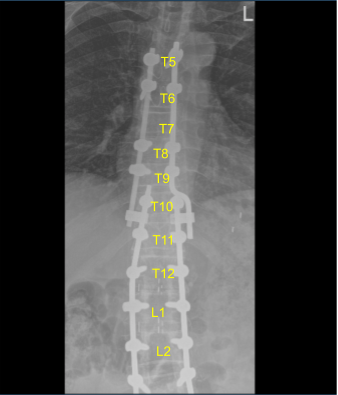

AP and lateral x-rays and final CT scan showed appropriate positioning of all the hardware. Morselized allograft with bone morphogenic protein was packed in lateral gutters on the left side for new fusion arthrodesis. Vancomycin powder was applied. Hemostasis was confirmed. A medium size Hemovac drain was tunneled in a subfascial manner and secured to the skin with a nylon suture.

Sagittal View of Thoracic spine postoperative X-ray

Axial view Thoracic spine postoperative X-ray